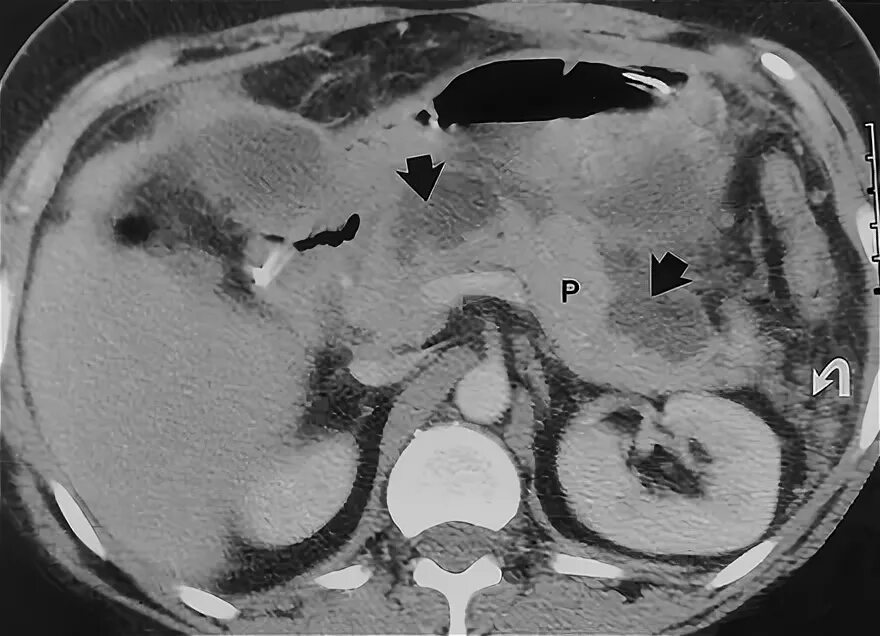

Инфильтрация паранефральной клетчатки на кт. параколитическая клетчатка кт. парапанкреатическая клетчатка инфильтрирована. перипанкреатический инфильтрат.Кт при остром панкреатите. парапанкреатическая клетчатка. кт диагностика панкреатита. острый отечный панкреатит кт.Парапанкреатическая клетчатка. поддиафрагмальное пространство. внебрюшинное поддиафрагмальное пространство. парапанкреатическая клетчатка инфильтрирована.Парапанкреатическая клетчатка что это значитКлетчатка анатомия. понятие о клетчатке в анатомии. основы клинической анатомии. клетчатка понятие.Парапанкреатическая клетчатка что это значитПарапанкреатическая клетчатка. парапанкреатическая клетчатка инфильтрирована. парапанкреатическая инфильтрация. парапанкреатическая клетчатка дифференцирована.Парапанкреатическая клетчатка что это значитПарапанкреатическая клетчатка что это значитХронический панкреатит на кт. парапанкреатическая клетчатка на кт. кт поджелудочной железы. поджелудочная железа на рентгенограмме.Парапанкреатическая клетчатка что это значитПарапанкреатическая клетчатка что это значитПарапанкреатический инфильтрат. парапанкреатическая клетчатка дифференцирована.Парапанкреатическая клетчатка что это значитПарапанкреатическая клетчатка что это значитПарапанкреатическая клетчатка поджелудочной железы. отек парапанкреатической клетчатки. парапанкреатическая инфильтрация. острый деструктивный панкреатит кт.Парапанкреатическая клетчатка что это значитПарапанкреатическая клетчатка что это значитПарапанкреатическая клетчатка что это значитПарапанкреатическая клетчатка что это значитПарапанкреатическая клетчатка что это значитПарапанкреатический инфильтрат. перипанкреатический инфильтрат. парапанкреатическая псевдокиста на кт.Парапанкреатическая клетчатка что это значитПарапанкреатическая клетчатка что это значитПарапанкреатическая клетчатка что это значитПарапанкреатическая клетчатка что это значитПарапанкреатическая клетчатка что это значитПарапанкреатическая клетчатка что это значитПарапанкреатическая клетчатка что это значитПарапанкреатическая клетчатка что это значитПарапанкреатическая клетчатка что это значитПарапанкреатическая клетчатка поджелудочной железы. перипанкреатический инфильтрат. осложнения острого панкреатита презентация. перипанкреатическая клетчатка.Парапанкреатическая клетчатка что это значитКисты и свищи поджелудочной железы. инфильтрация парапанкреатической клетчатки. истинные кисты поджелудочной железы классификация. парапанкреатическая клетчатка поджелудочной железы.Парапанкреатическая клетчатка что это значитПарапанкреатическая клетчатка что это значитПарапанкреатическая клетчатка что это значитПарапанкреатическая клетчатка что это значитПарапанкреатическая клетчатка что это значитПарапанкреатическая клетчатка что это значит